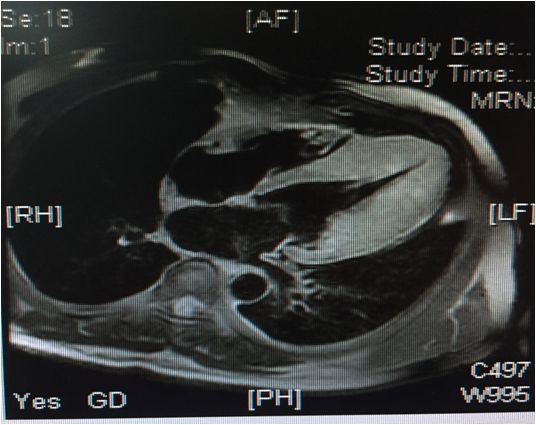

左房饱满,左室不大,前间隔及其余左室各中远段及心尖部增厚(最厚16-21mm)

舒张期心尖呈“黑桃尖”样改变,收缩末左室腔中部几近闭塞,心尖室腔呈裂隙样

左室基底段厚度大致正常或高限,收缩功能大致正常,左室流出道未见梗阻征象

右房、右室不大,右室壁未见脂肪浸润,右室收缩功能大致正常,右室流出道未见梗阻征象

二尖瓣少量反流,三尖瓣及主动脉瓣活动未见异常,心包无增厚,主肺动脉直径25mm,同水平升主动脉直径28mm

心肌首过灌注左室心尖部可见心内膜下灌注减低

延迟扫描室间隔远段及左室心尖部可见心内膜下强化信号